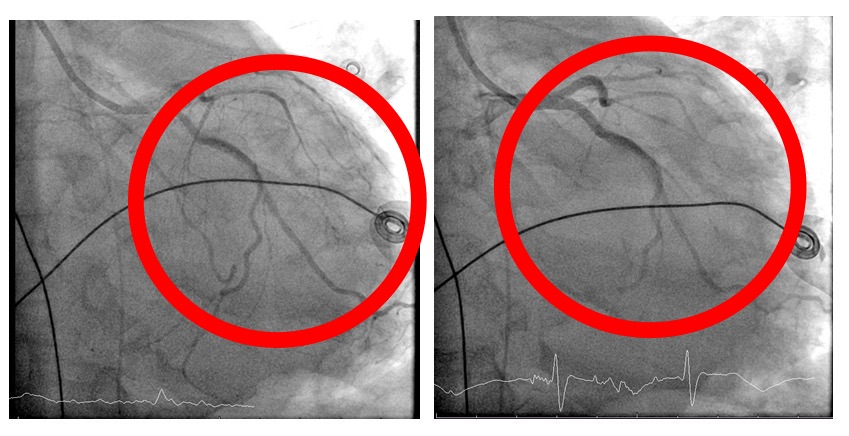

心臟內科張偉俊醫師立即安排緊急心導管檢查,歷時七小時完成高難度冠狀動脈鈣化旋磨與與震波氣球治療,成功打通三條嚴重阻塞之冠狀動脈並完成支架置放。(記者孫義方攝)

在葉克膜支持下,心臟內科張偉俊醫師立即安排緊急心導管檢查,歷時七小時完成高難度冠狀動脈鈣化旋磨與震波氣球治療(Rota-Shock策略),成功打通三條嚴重阻塞之冠狀動脈並完成支架置放,同步放置主動脈內氣球幫浦(IABP),以提升心臟輸出量、減輕心臟負荷並穩定血流動力。

院方安排患者進行緊急心導管檢查,歷時七小時完成高難度冠狀動脈鈣化旋磨與震波氣球治療。(記者孫義方攝)